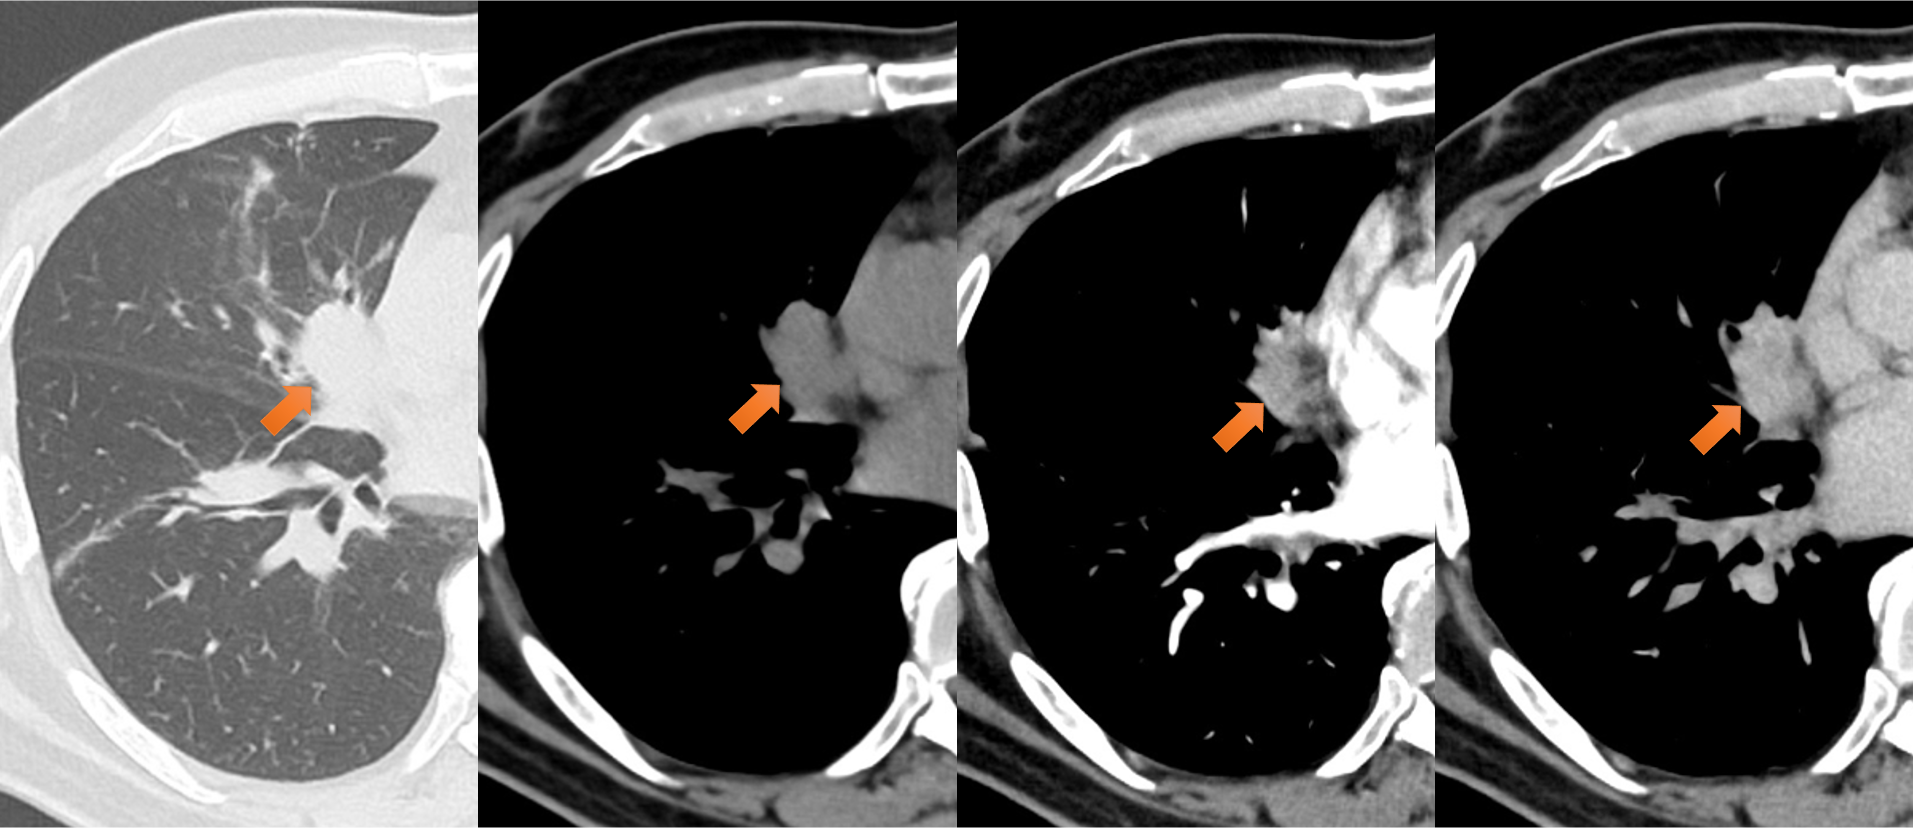

図5.右中葉腫瘤

右中葉中枢側に29mm大の腫瘤あり、造影で漸増性の増強効果を認めた。膵尾部病変と類似しており、転移と考えられた。右中葉B5末梢側にかけて軟部影が充満しており、腫瘍の気管支内進展が疑われた。

図6.肺動脈造影欠損像

右肺下葉動脈(A8)、左肺上下葉動脈(A3やA8、A9など)に造影欠損あり、造影で一部、増強効果を伴っており、腫瘍塞栓/血栓が疑われた。